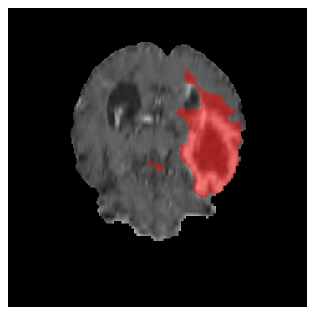

Appendix A Qualitative results

Figures 4 and 5 present the segmentation results for a patient from the BRATS dataset, visualized on a randomly selected slice. Figure 4 illustrates how tumor segmentation evolves over multiple episodes in S1 across different approaches including cumulative, naive, our approach, and the best buffer-free strategy (SI, =2). The cumulative approach, which trains on all encountered datasets together, maintains segmentation consistency across episodes but introduces significant amounts of false positives, particularly in the upper left area of the brain images. These misclassifications highlight its inability to generalize well across datasets despite access to all previous data. The naive approach, which learns sequentially without any continual learning strategy, suffers from severe catastrophic forgetting. While it initially segments well, performance deteriorates over episodes, leading to a near-complete loss of segmentation capability by the final episode. The SI (=2) approach, a regularization-based buffer-free CL strategy, performs reasonably well in early episodes but shows a significant performance decline over time. By the last episode, much of the tumor was no longer segmented, indicating difficulty in retaining prior knowledge. In contrast, our proposed approach initially produces more false positives but progressively refines its segmentation. By the final episode, it accurately retains the tumor region while minimizing misclassifications, demonstrating strong knowledge retention and adaptability across episodes. This suggests that our approach effectively mitigates catastrophic forgetting while maintaining segmentation performance over sequential learning.